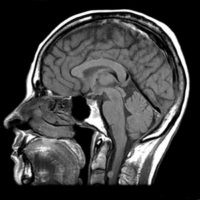

RMN Cerebral Bucuresti

RMN CEREBRAL : În ce simptome ai nevoie de un RMN la cap?